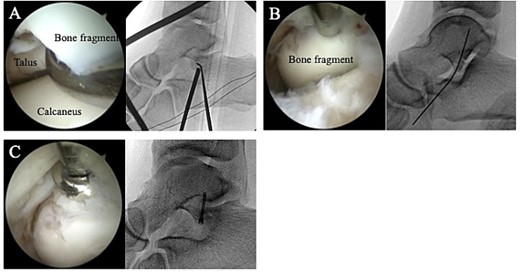

Postoperatively, a non-weightbearing short leg splint was postoperatively applied for 2 weeks. Active and passive range of motion exercises of the ankle were permitted at 2 weeks postoperatively. Partial-weightbearing was allowed at 4 weeks postoperatively, and full-weightbearing at 6 weeks postoperatively. The patient was allowed to jog 8 weeks after surgery. After confirming that bone union was obtained on non-contrast CT (Fig. 5) and tenderness on the lateral side of the ankle had resolved, the patient was allowed to return to his original sport at 12 weeks postoperatively. Two years after surgery, the patient remained a competitive basketball player with no symptoms. Additionally, the AOFAS score had improved to 100 points.

A non-contrast CT taken at 12 weeks postoperatively showed bone union in the coronal (A) and sagittal (B) views.